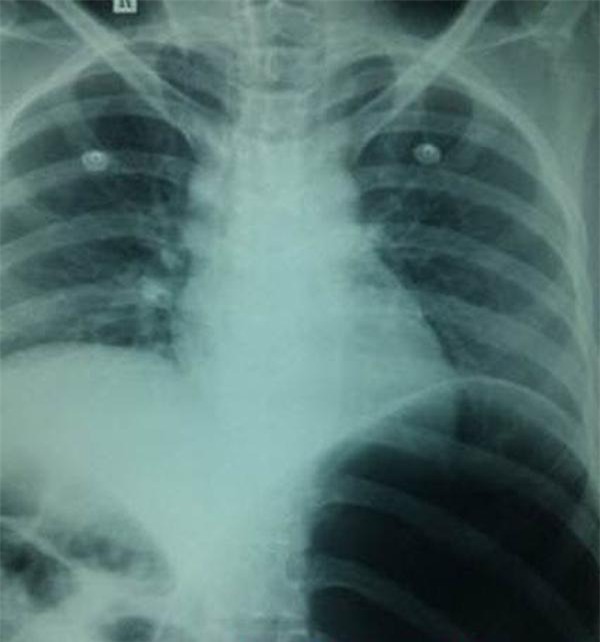

Được biết trước đó, người đàn ông này đã nhập viện trong tình trạng bị đau bụng dữ dội. Kết quả chụp CT cho thấy hàng trăm viên sỏi đang nằm trong thận của ông.